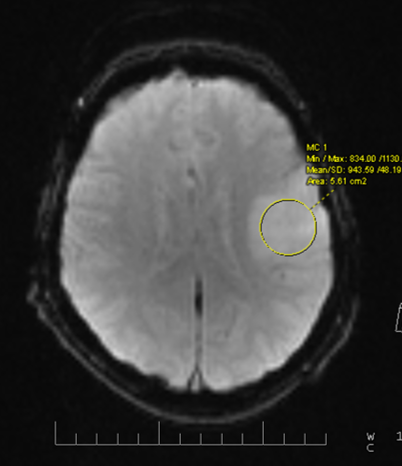

Затемнение на мрт

Затемнение на мрт 140 фото